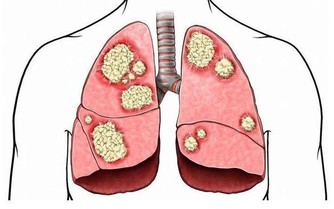

2、發紺

這是一種身體特定區域變成紫色的醫學症狀。

皮膚顏色青紫說明身體某個部位得不到充足的氧氣,青紫的原因可以是任何疾病或者紊亂。

可以很容易從身體皮膚表面看到發紺。

急性發紺的主要根源是心臟衰竭,窒息,休克,左心衰竭等。

此外,有一些原因可導致慢性發紺。

如肺部疾病,慢性阻塞性肺病,先天性心臟病和心臟衰竭等。